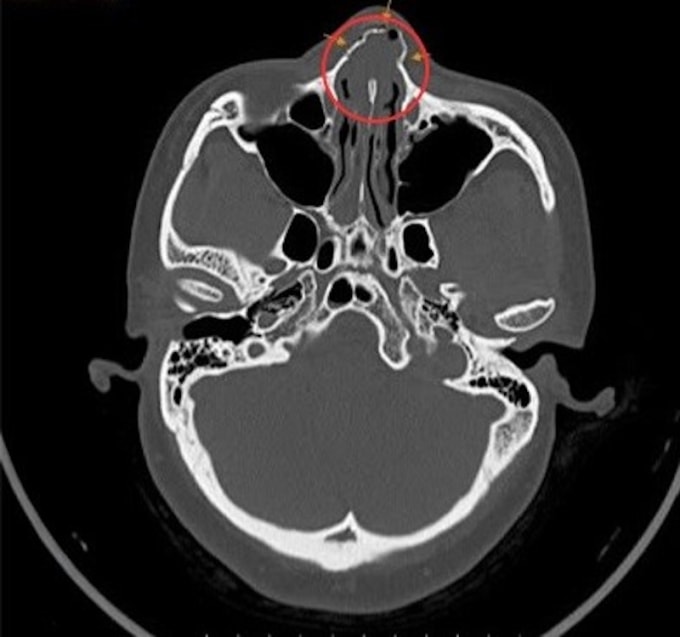

BS.CKI Châu Trà Linh, Trung tâm Tai Mũi Họng, Bệnh viện Đa khoa Tâm Anh TP HCM, cho biết chị Hàn nhập viện trong tình trạng chảy máu mũi đã cầm, đau vùng mũi và má trái, ù tai. Bác sĩ nội soi tai mũi họng ghi nhận vách ngăn mũi lệch, khe sàn mũi hai bên đọng dịch kèm máu tươi lẫn máu cũ. Kết quả chụp CT vùng hàm mặt cho thấy xương chính mũi gãy kín thành nhiều mảnh, chấn thương phần mềm vùng má bên trái, chấn thương răng.